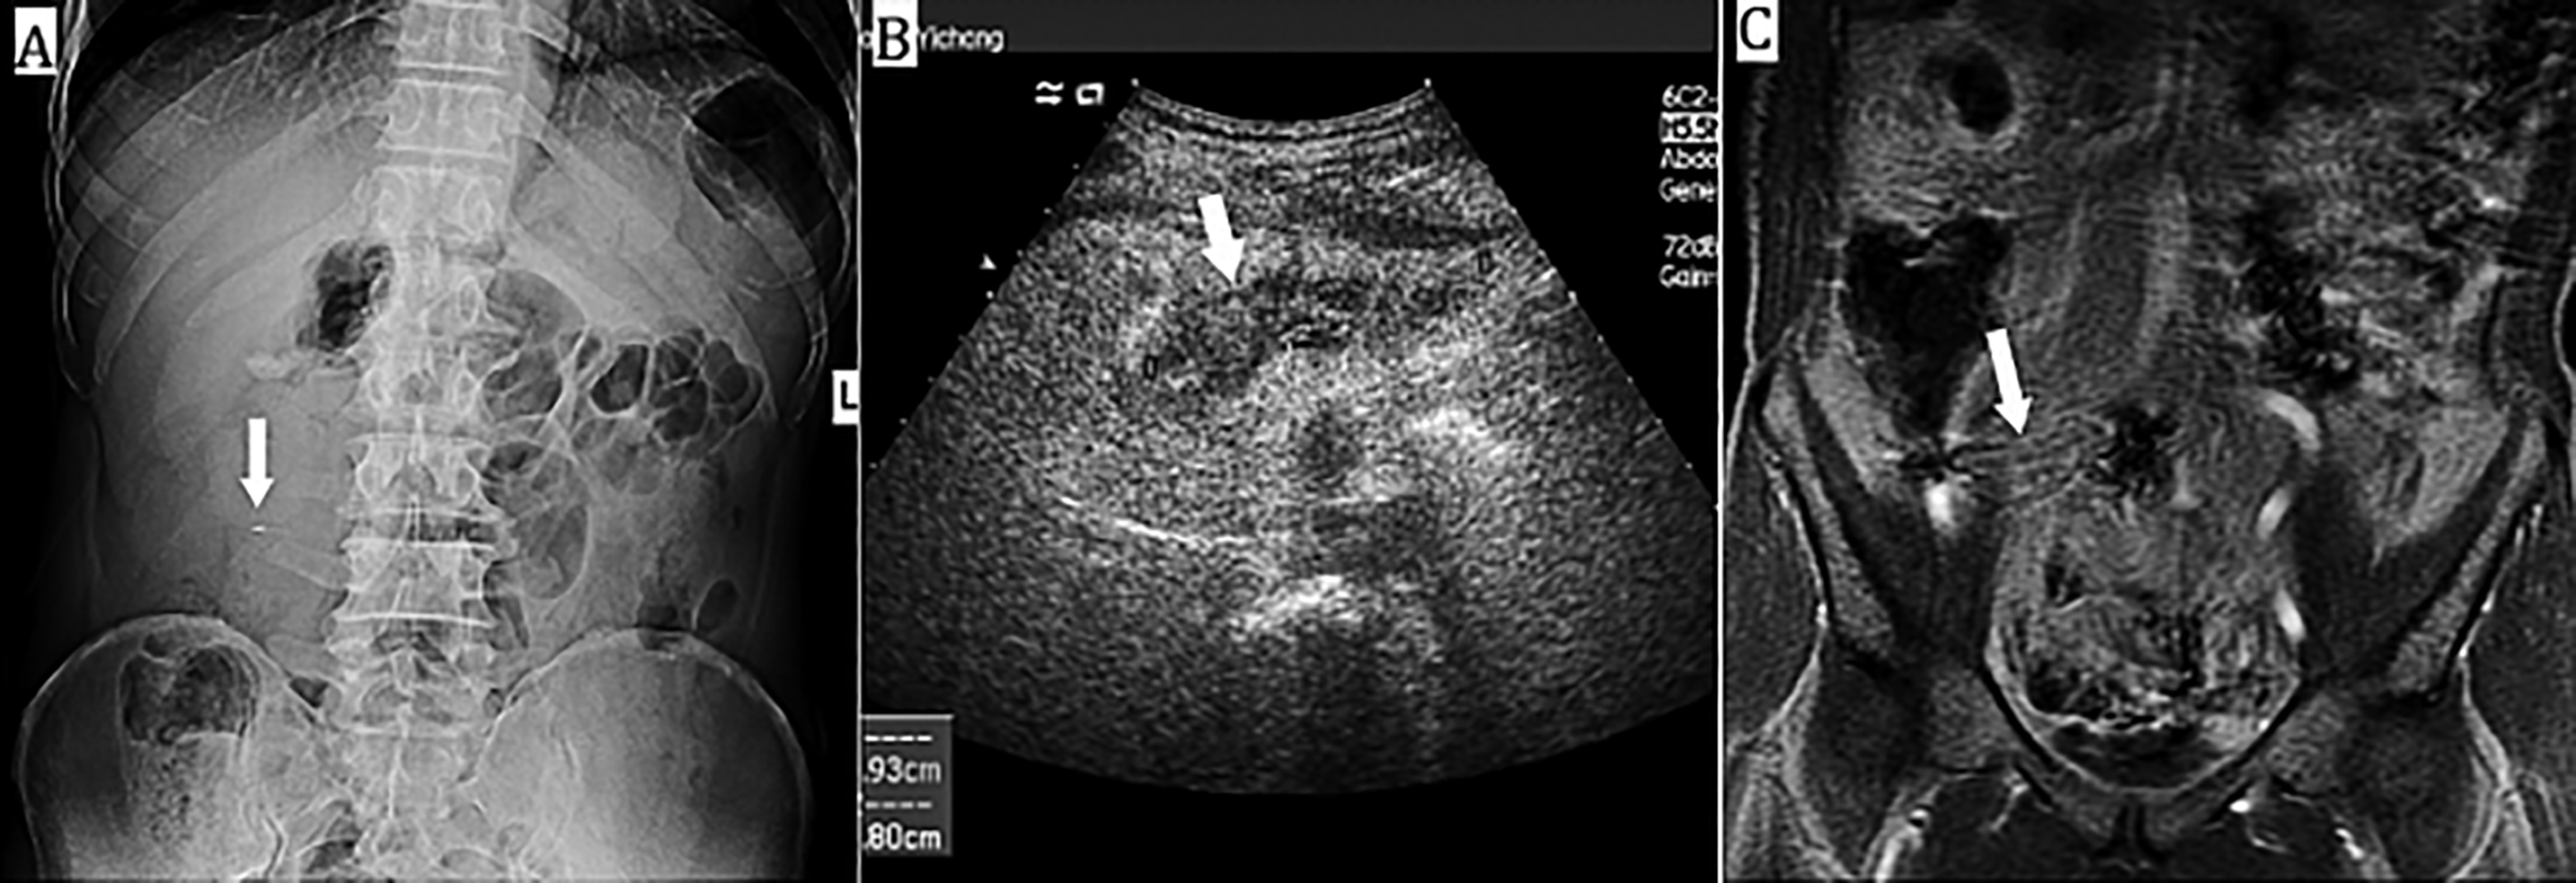

On admission, the temperature was 36.8℃, the heart rate was100 beats/min, the blood pressure was 135/90 mmHg, the respiratory rate was 21 breaths/min, and the oxygen saturation was 97% on ambient air. In the abdominal examination, a 10×10 cm mass was palpable in the right abdomen, with positive tenderness and no rebound pain. In the laboratory tests, white blood cell count was 9100/mm3, C-reactive protein, 8.13 mg/dl, red blood count, 437×104/mm3, and amylase, 72 IU/L. There were no other abnormalities, including occult blood in the stool, or elevated tumor markers. Chest radiography showed no abnormalities. Abdominal radiography showed a linear calcified structure about 3.5 × 0.2 cm in the right abdomen (Figure 1A), and no free gas under the diaphragm. Abdominal ultrasonography showed intestinal echo in the right mid-clavicular line in the abdominal cavity at the level of the umbilical horizontal line (Figure 1B). A magnetic resonance imaging (MRI) scan of the abdomen showed a linear, dense foreign body, seemingly penetrating from the anterior wall of the gastric antrum. The abnormal signal on the right side of the abdomen, likely inflammatory in origin with the formation of the encapsulated abscess was also observed (Figure 1C). Following the review of the whole case and consideration of extraneous matter ingestion, the patient remembered eating fish 6 months back.

Figure 1: (A) Abdominal radiography shows a linear calcified body in the right abdomen (arrow). (B) Abdominal ultrasonography shows intestinal echo in the right mid-clavicular line in the abdominal cavity at the level of the umbilical horizontal line (arrow). (C) Abdominal MRI scan shows a linear, dense foreign body wrapped by greater omentum (arrow).